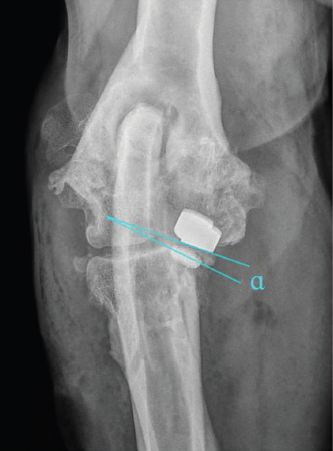

Cranio-caudal overlap of both implants was measured on ML views (Figs. 3 and 4).

Fig. 3. Determination of long bone axis as well as joint rotation center for measurement of cranio-caudal humero-ulnar implant overlap turquoise arrows: midpoints between cortices at 50% and 30% of the humeral and radial bone length; blue arrows: longitudinal bone axis of humerus and radius; green cross: center of elbow joint rotation, identical with center of humeral condyle; red lines: cranial and caudal edge of the humeral and ulnar implants.

Fig. 4. Measurement of simulated elbow joint extension angle for six states of cranio-caudal humero-ulnar implant overlap, starting with full extension. (A) No overlap between ulnar and humeral implant, with the ulnar implant just caudal to the humeral one; (B) coverage of the cranial half of the ulnar implant (50%); (C) largest extension angle with 100% ulnar coverage; (D) smallest extension angle with 100% ulnar coverage; (E) coverage of the caudal half of ulnar implant (50%); and (F) no overlap between ulnar and humeral implant, with the ulnar implant just cranial to the humeral one. α: measured extension angle.

The results of cranio-caudal implant overlap measurements in the sagittal plane are illustrated in Table 1.

ROM values for 50% and 100% overlap for one, two, or three implants, respectively, are illustrated in Table 2.

Table 1. Cranio-caudal Implant Overlap. Starting with full extension, the overlap of the implants in the sagittal plane began at 169.1° (SD: 3.5°) of elbow extension. Fifty percent of the UImpl were covered by HImpl at 153.8° (SD: 24.0°) of extension. Full coverage of the UImpl was present between 136.3° (SD: 22.6°) and 103.7° (SD: 20.4°). Implant overlap was reduced again to 50% at an extension angle of 88.9° (SD: 19.5°) and coverage was lost at an angle of 72.6° (SD: 20.3°).

Table 2. Implant overlap ROM. With one UImpl overlap of 50% or 100% was achieved within a ROM of 58.5° (IQ: 54.0°–66.0°) and 31.0° (IQ: 26.0°–35.0°), respectively. With two UImpl this increased to 96.5° (IQ: 82.0°–111.0°) and 40.8° (IQ: 26.0°–55.5°), respectively, while three UImpl resulted in a ROM with 50% and 100% of overlap at 106.0° (IQ: 89.0°–123.0°) and 55.0° (IQ: 42.0°–68.0°), respectively.